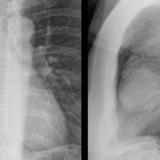

Case 8b Thymoma Lat

Date: 03/27/2009

Views: 14171